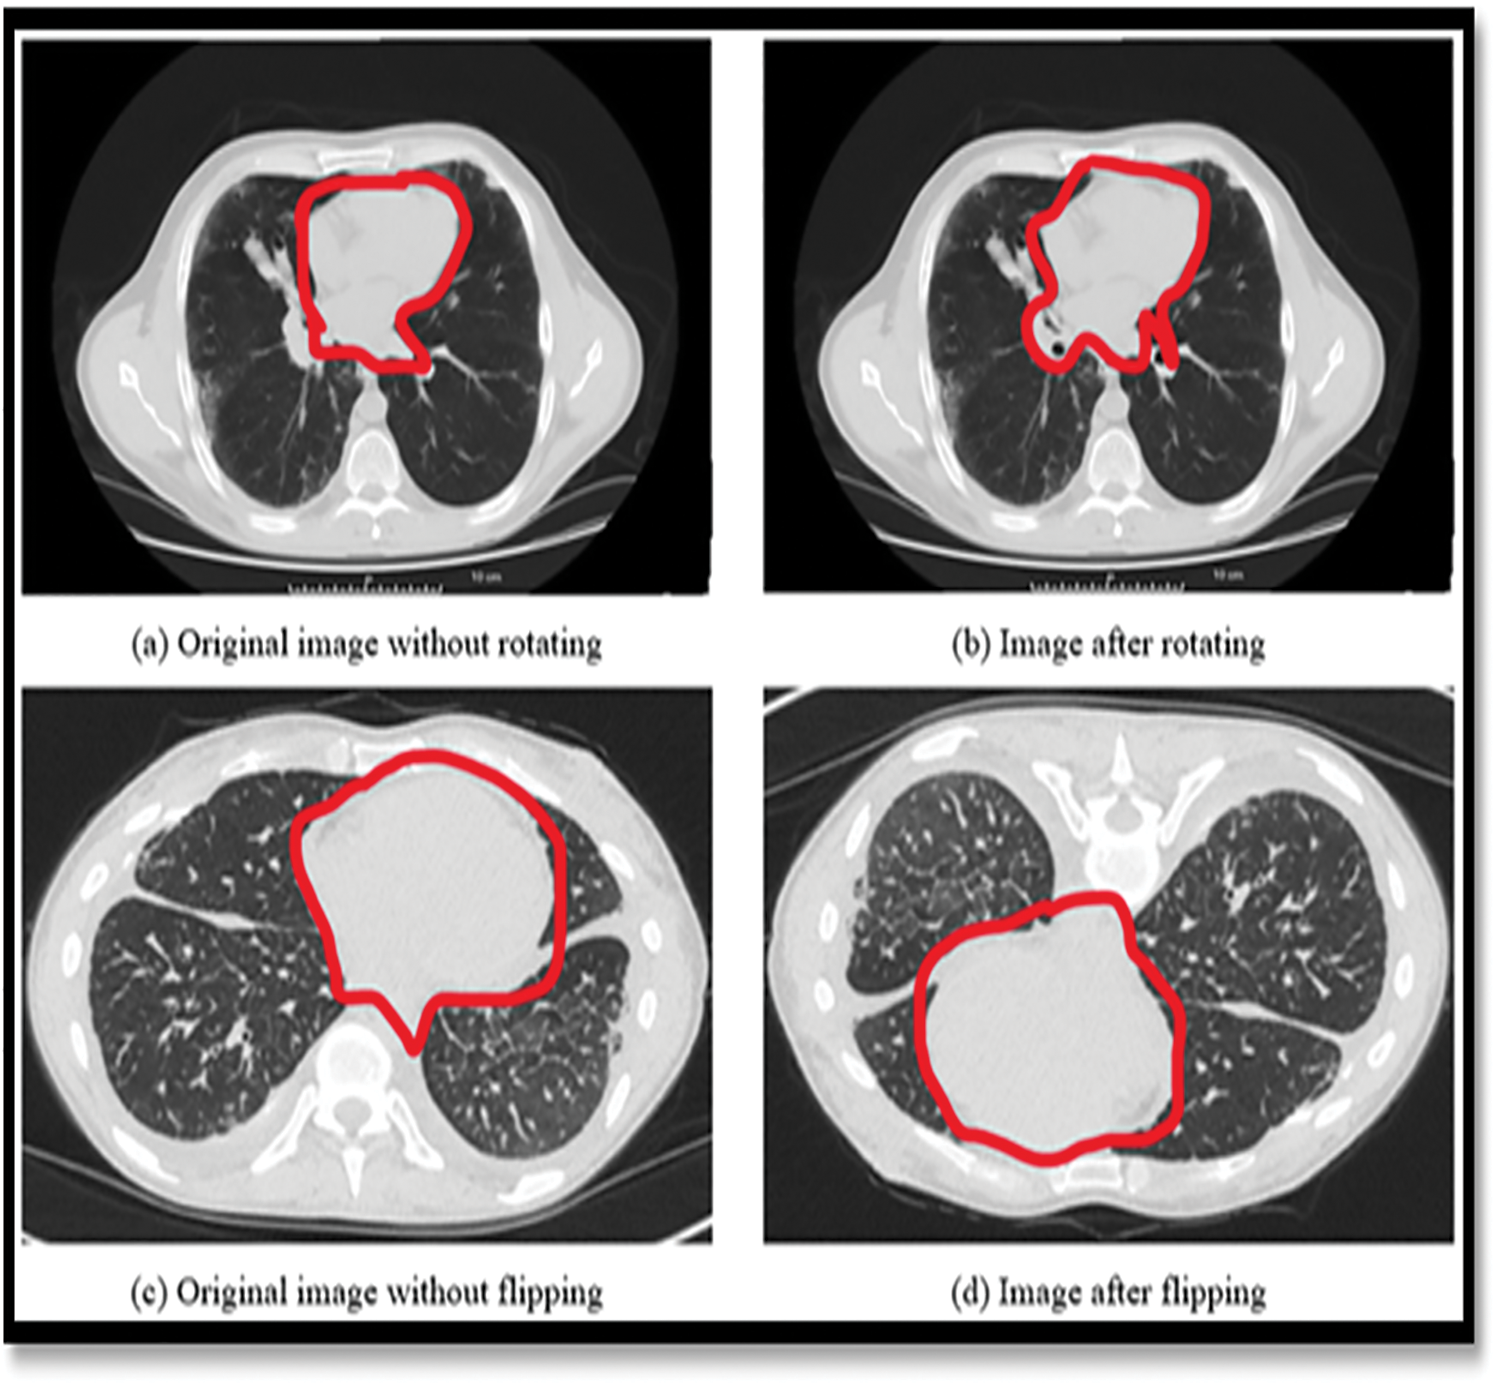

Lung cancer is the leading cause of mortality in the world [1], affecting both men and women equally. According to the American Cancer Society, 222,500 [2] new instances of lung cancer were diagnosed in 2020 and 155,870 individuals died as a result of the disease. The survival rate for colon cancer is 65.4%, whereas breast cancer has a survival rate of 90.35% and prostate cancer has a survival rate of 99.6% which is much lower than the overall survival rate of 65.4% [3]. It is possible that a lung nodule is an indication of lung cancer. Only 16% of cases are discovered in the early stages. If these nodules are discovered while they are still in their original location, the odds of survival increase from 10% to 65%–70%. Lung cancer is detected and treated with the use of imaging methods such as Multidetector X-ray Computed Tomography (MDCT) was shown in the Fig. 1. If you have a CT scanning [4] today, you will get a large amount of information. Performing all of this data segmentation and analysis by hand is difficult and time-consuming. It makes the work of the radiologist more complicated and time-consuming. It is possible that glancing at a large number of images can increase the likelihood of missing essential clinical criteria such as abnormalities.

Figure 1: Showing the limitations of the normal image-based segmentation

In order to address this issue, Computer-Assisted Diagnosis (CADx) and Computer-Assisted Detection (CADe) have been investigated as potential methods of assisting radiologists [5] with CT scans while also improving their diagnostic accuracy. For the last two decades, researchers from all around the globe have been focusing their efforts on strategies to increase the accuracy of lung nodule detection. The four major components of the CAD/CADe system are shown in Fig. 1. (1) The lungs are immediately divided into two halves. Selection of nodule candidates or division of nodules are two examples of nodule division. 3-Nodules and the many forms of nodules 4) It was discovered that the patient had lung cancer.